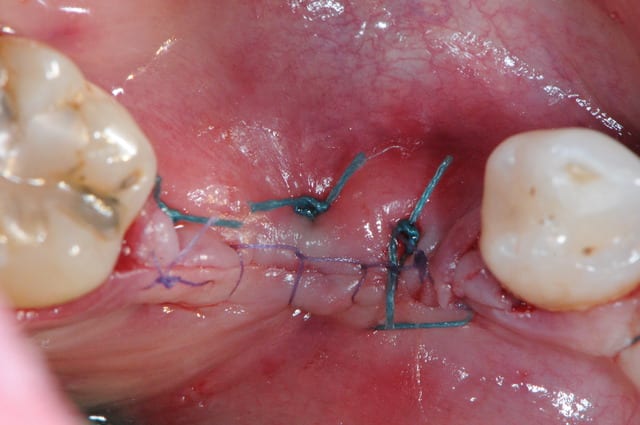

voici l'un des secrets pour une bonne réussite dans ce type d'intervention.

il faut absolument que les berges de la gencive n'aient aucune tension. donc il faut quelques points de chaipuki (photo1) puis réaliser la fermeture des berges (photo2)

les derniers fils peuvent être alors très fins (ici du 6/0)